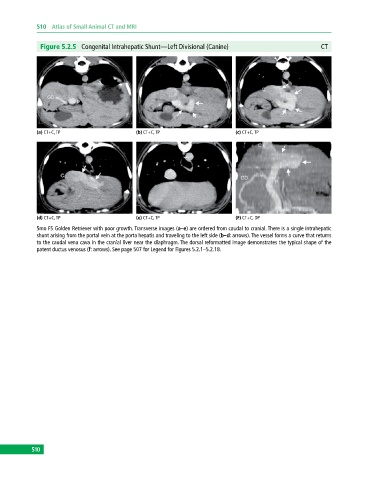

Figure 5.2.5 Congenital Intrahepatic Shunt—Left Divisional (Canine) CT

(a) CT+C, TP (b) CT+C, TP (c) CT+C, TP

(d) CT+C, TP (e) CT+C, TP (F) CT+C, DP

5mo FS Golden Retriever with poor growth. Transverse images (a–e) are ordered from caudal to cranial. There is a single intrahepatic

shunt arising from the portal vein at the porta hepatis and traveling to the left side (b–d: arrows). The vessel forms a curve that returns

to the caudal vena cava in the cranial liver near the diaphragm. The dorsal reformatted image demonstrates the typical shape of the

patent ductus venosus (f: arrows). See page 507 for Legend for Figures 5.2.1–5.2.18.